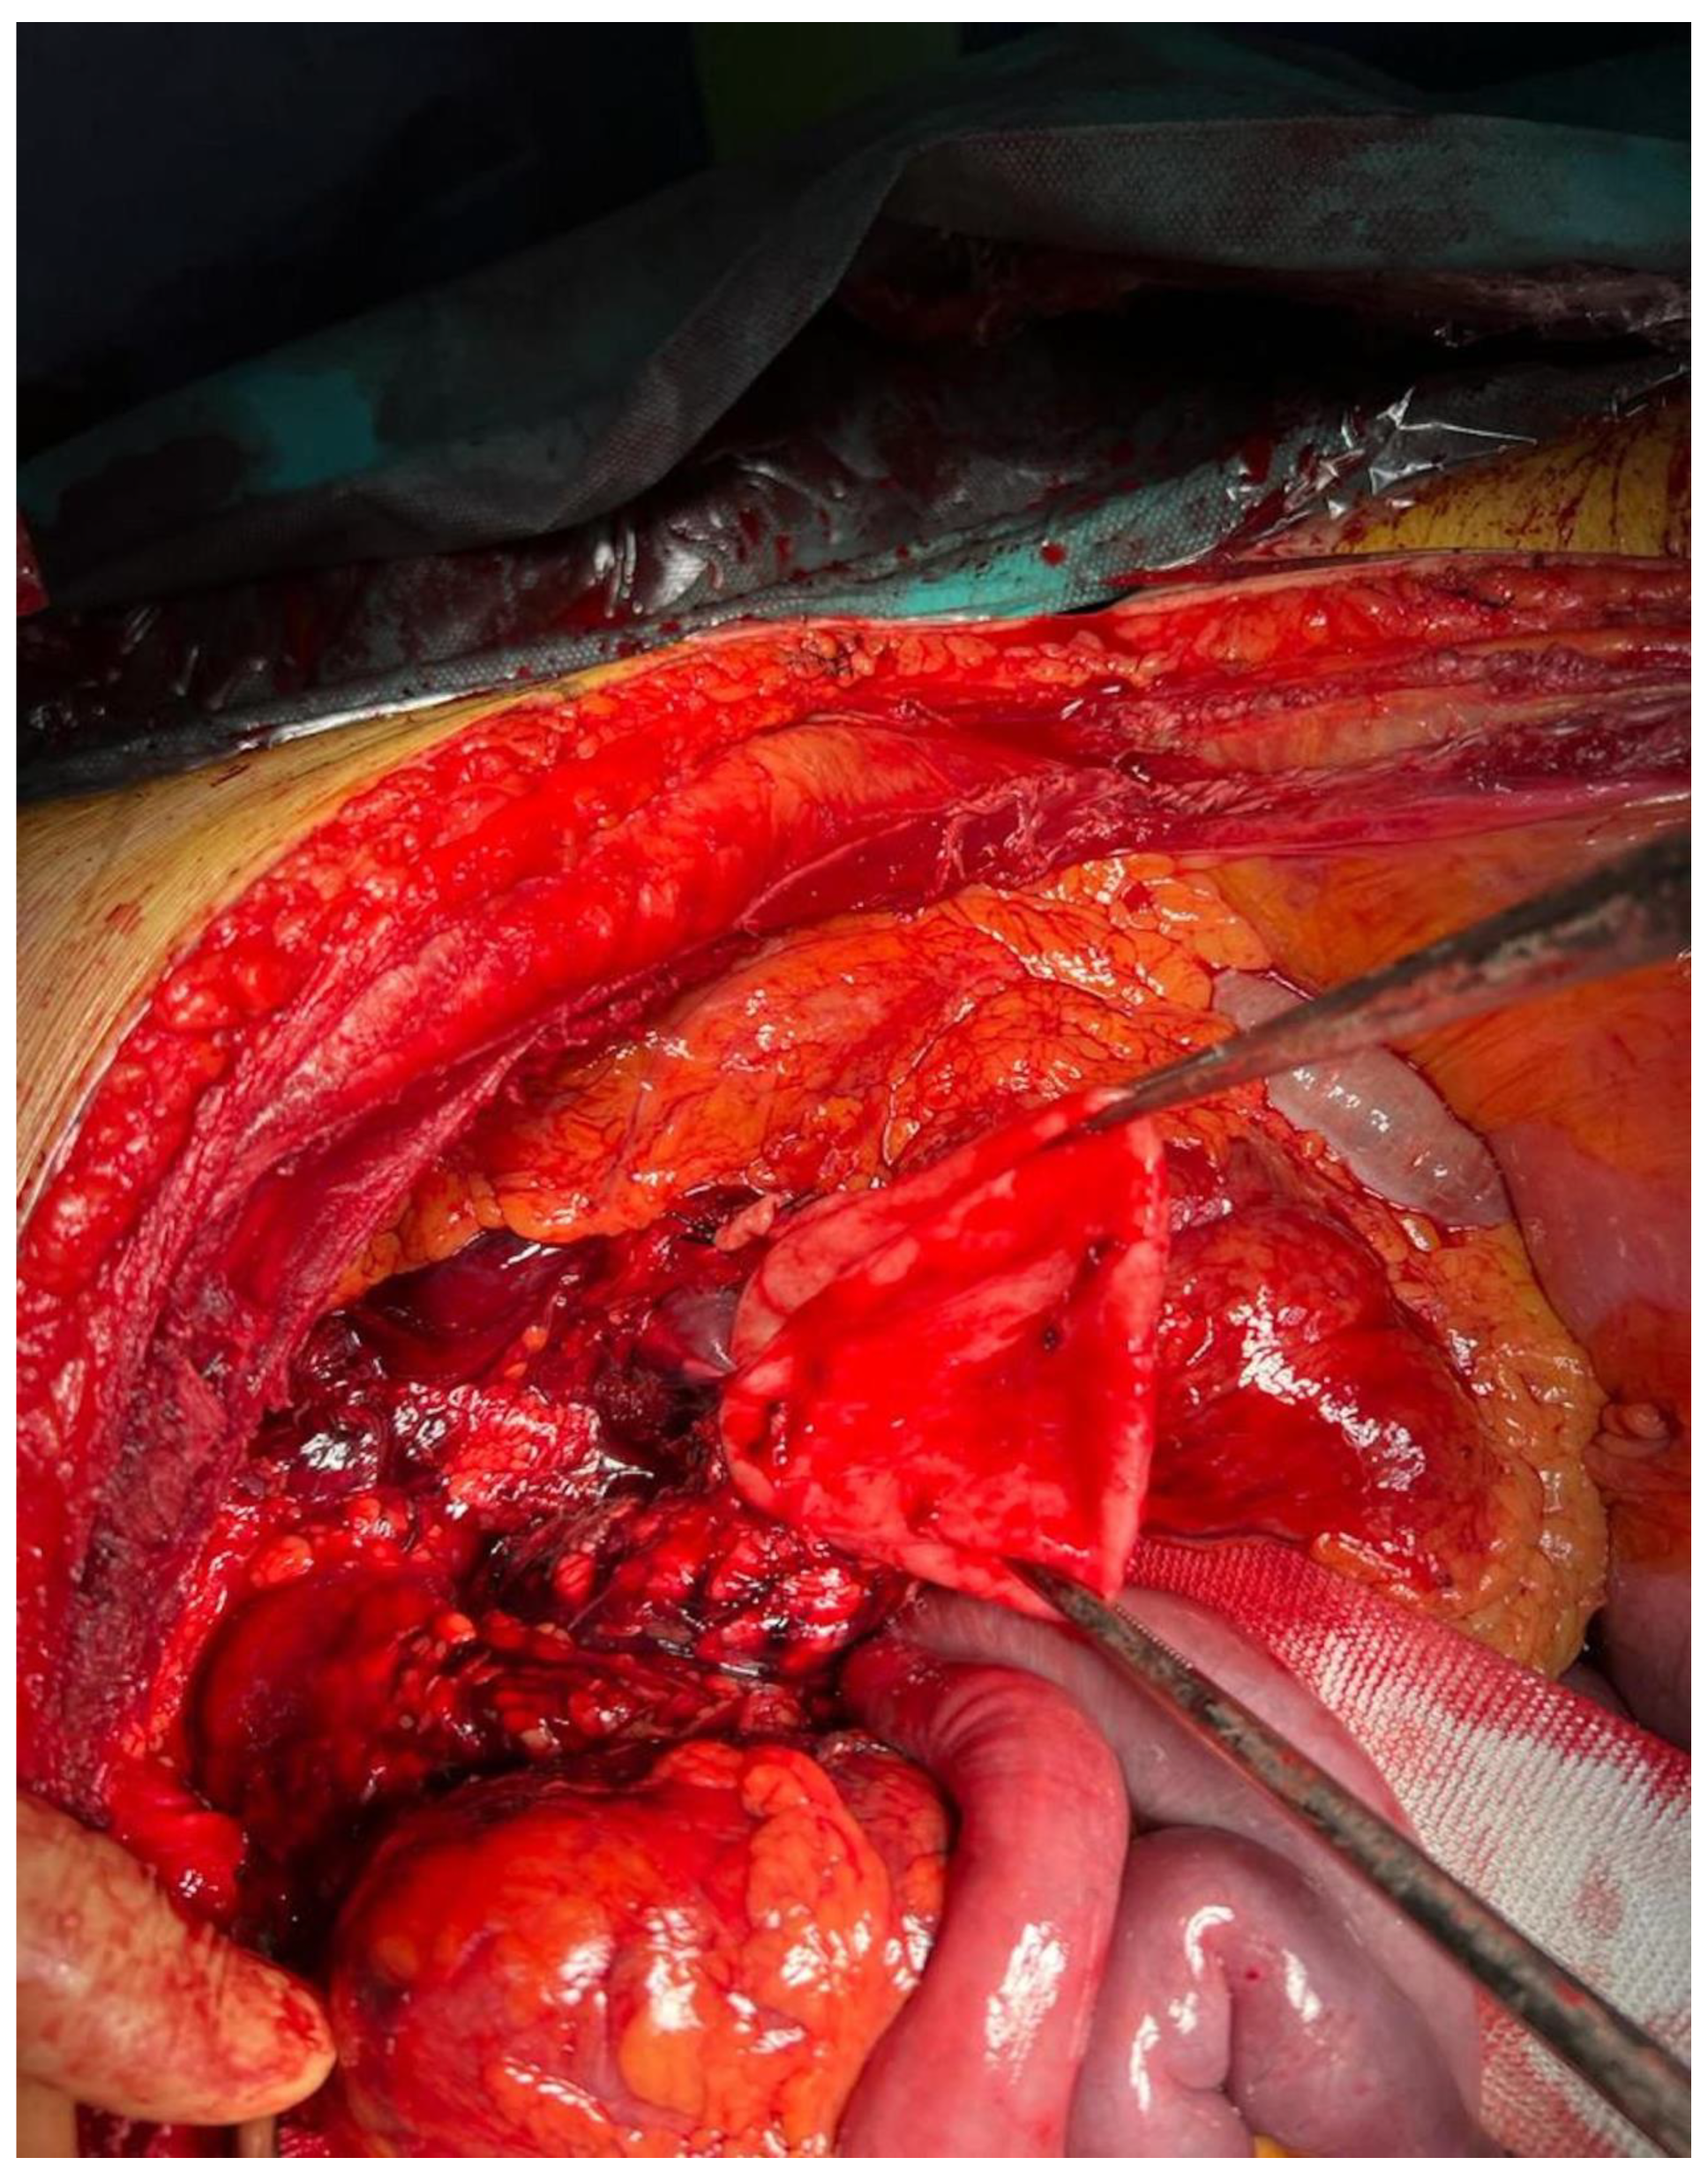

2.1. Case Report